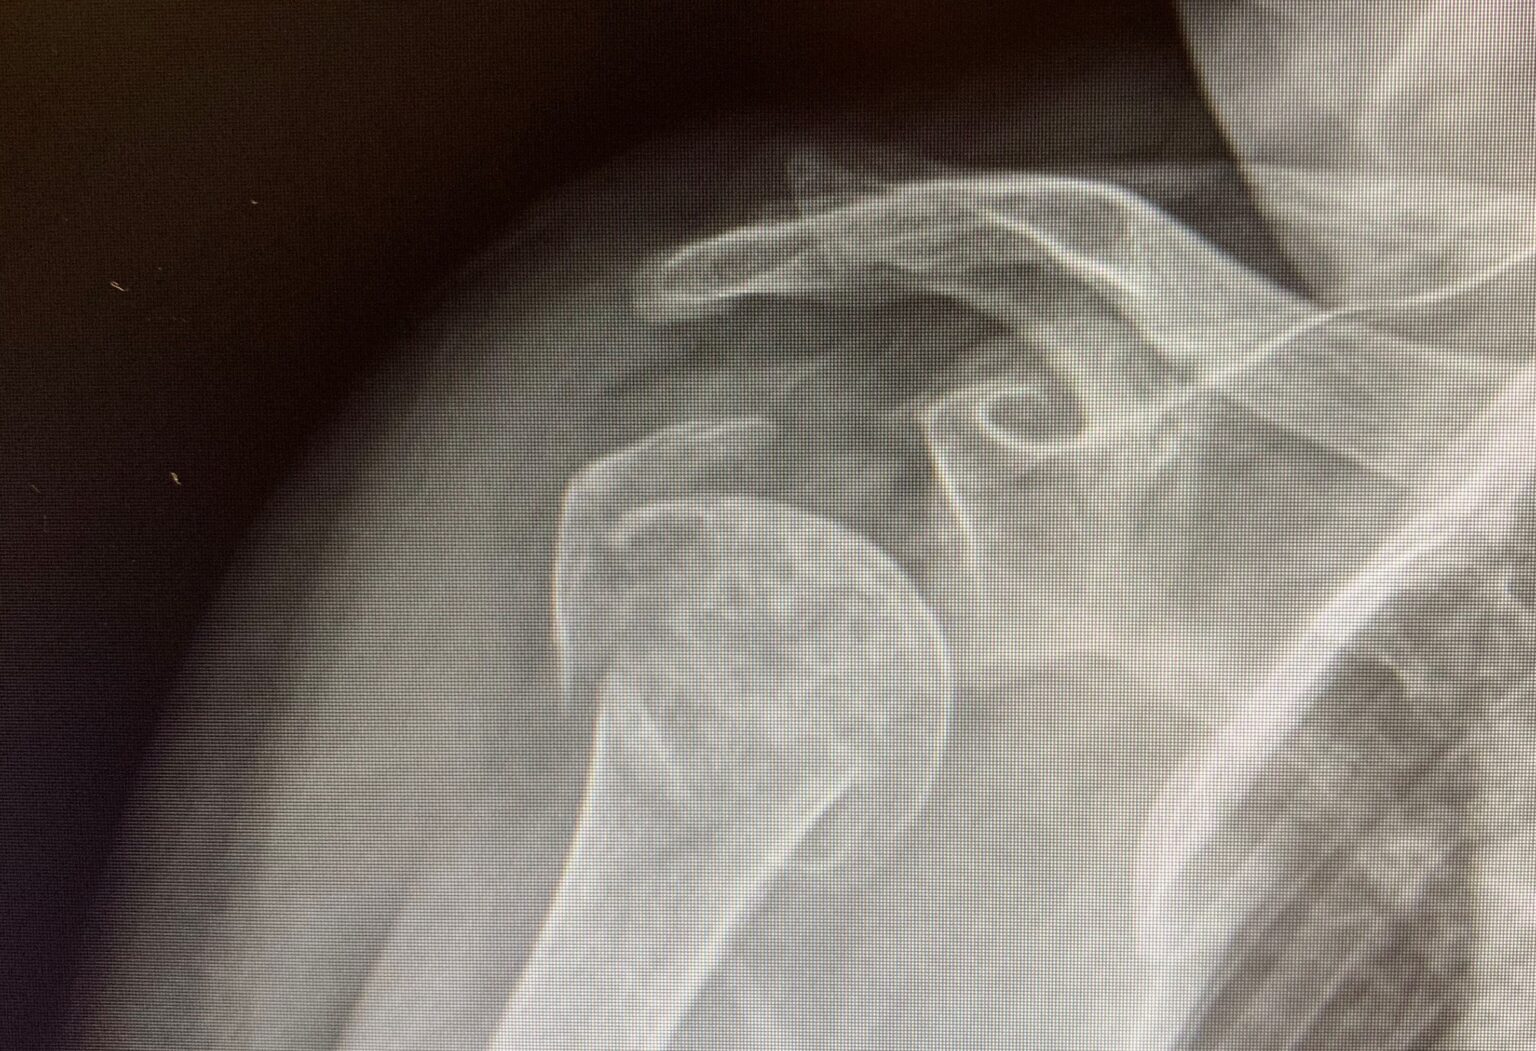

Shoulder Fracture Repair . Immobilization and physical therapy are the primary treatments for mild to moderate fractures or closed injuries. If there is significant damage to the humeral head which can’t be. Surgery for a shoulder fracture involves realigning the bones and then fixing them in place with either plates, screws or rods. Most fractures of the proximal humerus can be treated without surgery if the bone fragments are not severely out of position (displaced).

Surgery for a shoulder fracture involves realigning the bones and then fixing them in place with either plates, screws or rods. Immobilization and physical therapy are the primary treatments for mild to moderate fractures or closed injuries. If there is significant damage to the humeral head which can’t be. Most fractures of the proximal humerus can be treated without surgery if the bone fragments are not severely out of position (displaced).